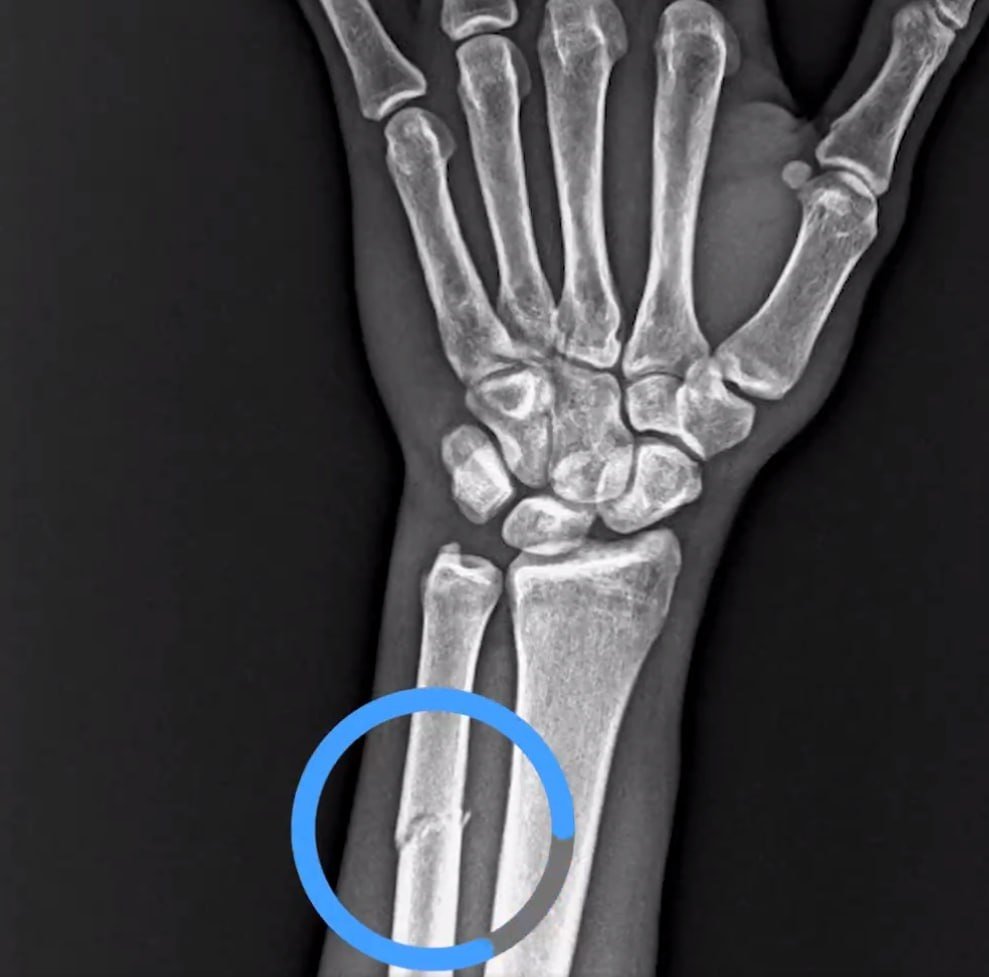

Ziraat Türkiye Kupası çeyrek final maçında Trabzonspor evinde RAMS Başakşehir’i 1-0 mağlup etti ve adını yarı finale yazdırdı. Bordo-mavili ekipte Paul Onucahu karşılaşmada kolundan sakatlandı. Çekilen MR’a göre yıldız oyuncunun kolunda kırık tespit edildi. Trabzonspor, resmi sosyal hesabından yaptığı paylaşımda tepkisini ifade etti.

VAR’da göremediğiniz pozisyonun röntgen görüntüsü⁰#AdaletinizBatsın pic.twitter.com/DwFUeeSXLf